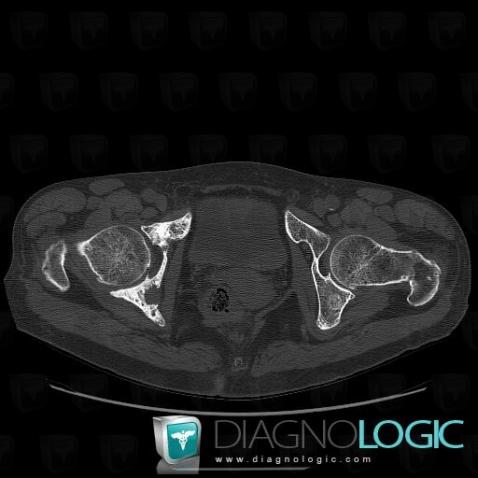

Metastasis, Ilium, CT

Here is the specific information in the key image above:

- Diagnosis Metastasis, Location(s) Ilium, with gamuts Cortical thickening